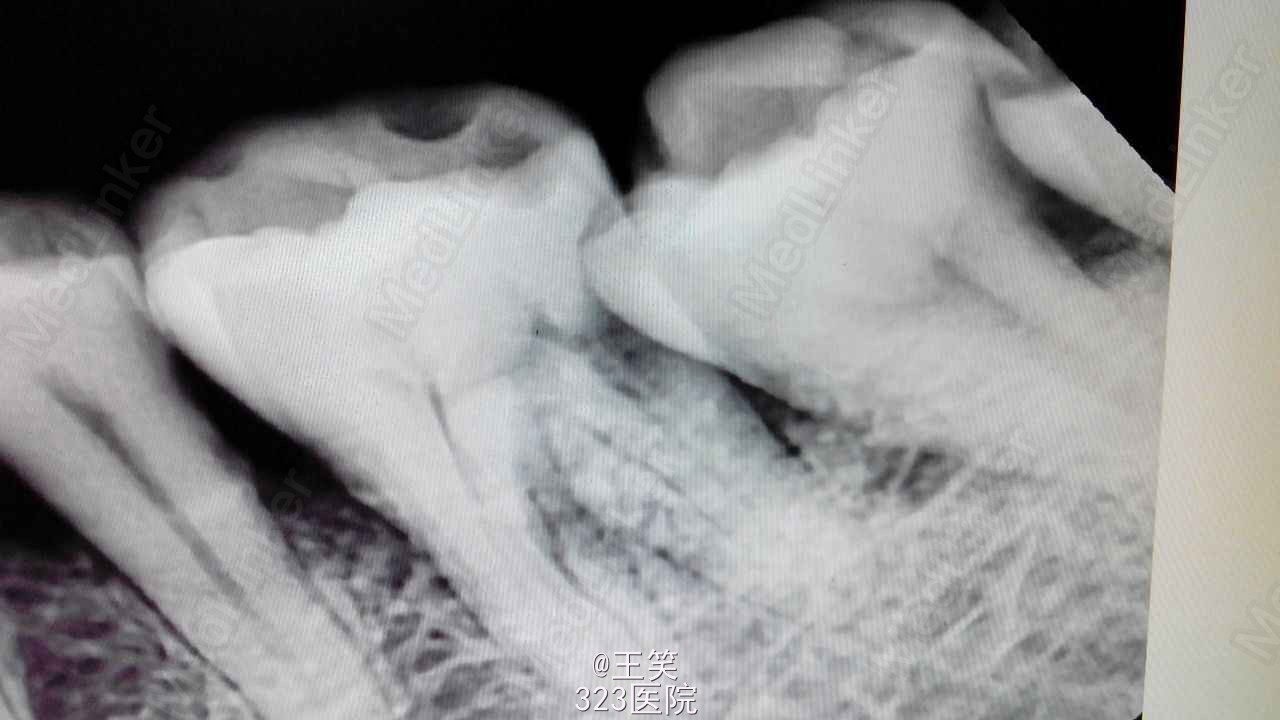

16近中颊部龋损,探深及龈下1mm,颌面白色充填物,冷(+) 松动(-) 叩(-)

17颊侧大面积龋损,缺损及龈下2mm,探(++) 叩(+) 冷(++) 松动(-)

x线示:16龋损近髓

17,45缺损及髓,根尖无明显异常

印诊:16深龋

17,45慢性牙髓炎